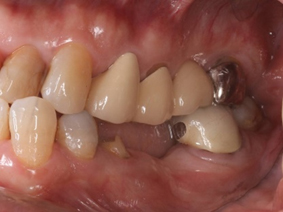

抜歯をした場合は、傷の治癒後に、ブリッジ・入れ歯・インプラントのいずれかの方法で補う治療が必要となります。

入れ歯(義歯)治療とは

歯を失った時の治療法として、「ブリッジ」 「インプラント」 「入れ歯(義歯)」があります。その中で失った歯の本数が多く、比較的短期間で治療が終わるのが入れ歯治療です。

歯を失ったままの状態にしていると咬み合わせていた歯が伸びてきたり、隣の歯が傾いてくるなど、歯並びや咬み合わせに影響を及ぼします。

インプラント治療とは

歯科の場合は、歯を失った時にそこを補うために、顎骨に人工歯根を埋め込んで、噛めるようにするインプラント治療が、広くおこなわれています。

歯を補う治療法には、主に「入れ歯」 「ブリッジ」 「インプラント」の3種類がありますが、インプラント治療はその中で唯一、天然の歯のような見た目および感覚が得られる治療法と言えます。